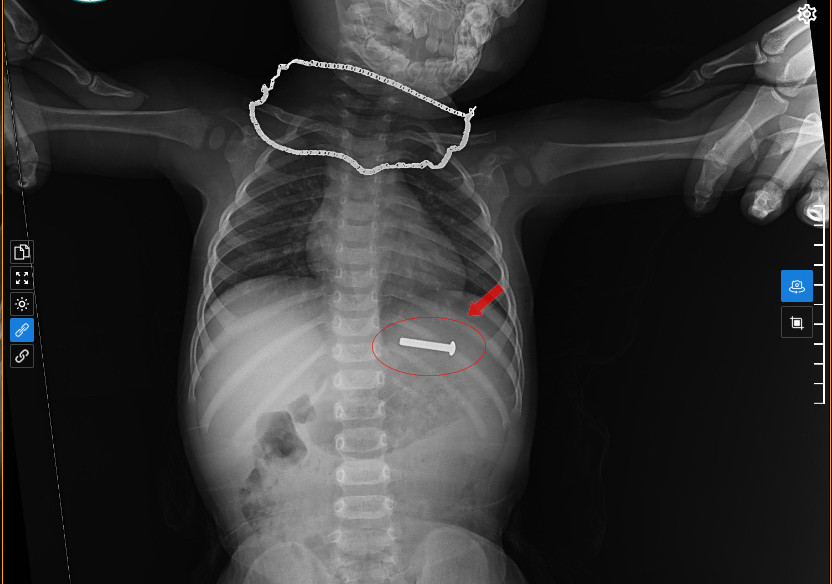

| Các bác sĩ tiến hành siêu âm, chụp X-Quang và phát hiện đinh vít sắt nằm trong dạ dày cháu bé. |

Tại bệnh viện, các bác sĩ đã tiến hành chụp X-quang, siêu âm và xác định đinh vít sắt đang nằm trong dạ dày của cháu bé nên tiến hành thủ thuật nội soi gắp dị vật. Sau 15 phút thực hiện, ekip nội soi đã gắp thành công chiếc đinh vít sắt ra ngoài an toàn.